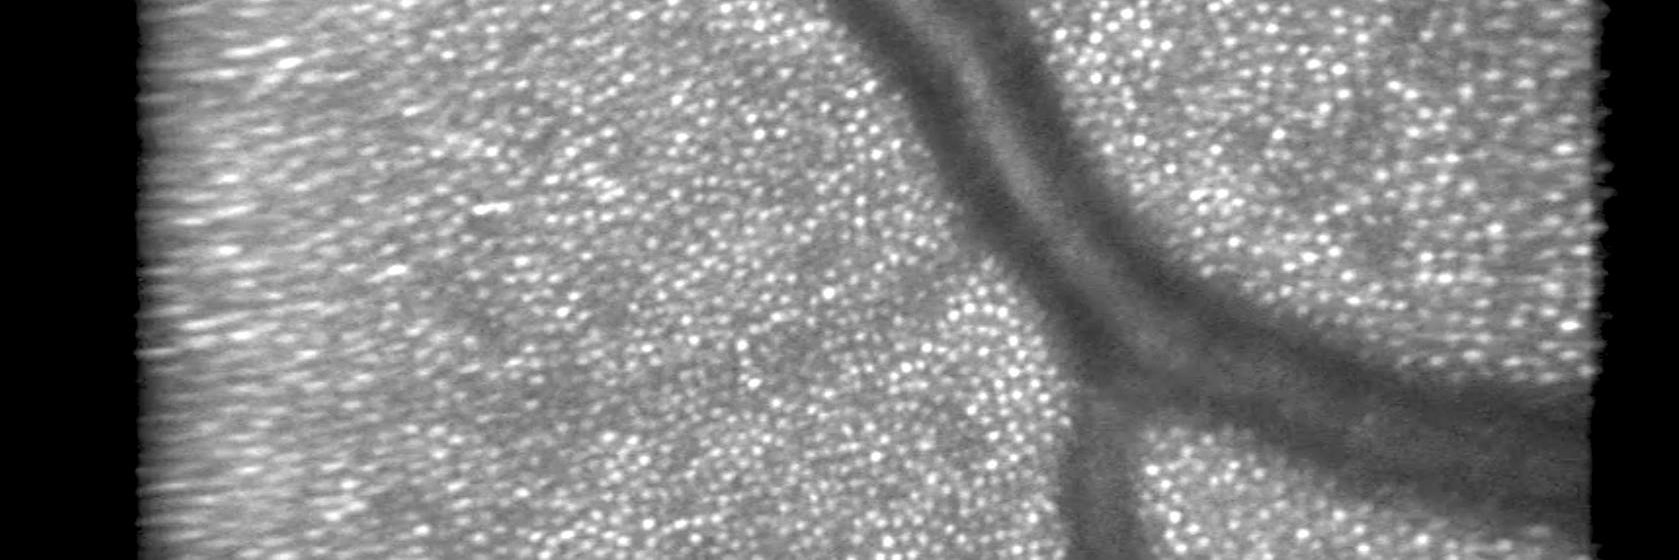

Excited to share 2p-prime, a novel physical pathway for multiphoton fluorescence generation that enables optical sectioning and excitation at red wavelengths with simple systems like continuous wave lasers. I founded @tripletimaging with @jdwong_campos to fully realize the potential of this tech and introduce a new paradigm for multiphoton fluorescence. We’re exciting real intermediary states, specifically driving forbidden triplet transitions, using picosecond and continuous wave lasers. Links to two pre-prints + explanation in the thread where we demonstrate 2p-prime with ps and CW lasers in dyes and living cells expressing fluorescent proteins. David thought of this idea, inspired by optical control of forbidden state transitions in atomic systems from his past life in quantum computing in the Monroe lab and as an early employee at @IonQ_Inc. In the limit, our approach could be optimized to replace all fluorescence microscopes with simple LED systems that can do rapid volumetric imaging with capabilities akin to existing 2p systems in optical sectioning, contrast, depth, and resolution. Low power, high throughput multiphoton imaging could enable moonshots like functional imaging of every synapse on a neuron or single cell resolution across an entire mouse cortex — datasets which are inaccessible now due to high powers required by ultrafast lasers. Fundamental insights may generate broad possibilities, and we’re investigating applications across multiple industries like diagnostics and 2p lithography. This is a white space in photophysics. No indicators have been designed or evolved for this process. We’re optimistic we’ll keep lowering power levels as indicators are optimized for these transitions, e.g. enhanced spin-orbit coupling.